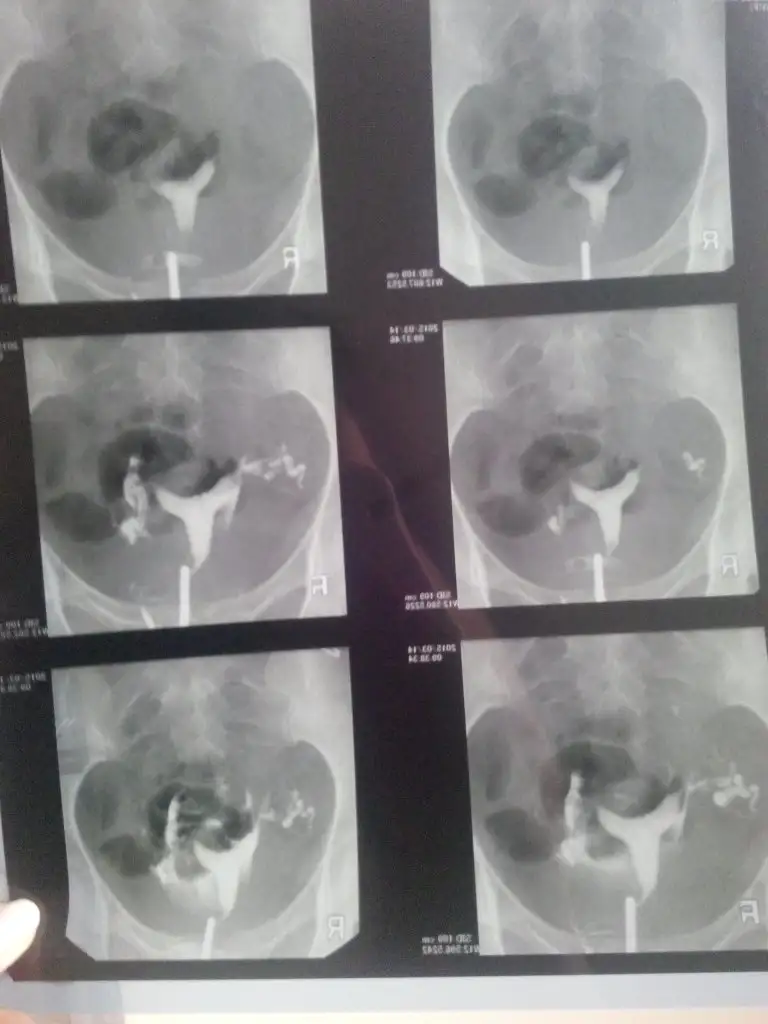

Uyutarak yaptirdim canim aci var uyandiktan sonra adet sancidi gibi az kanama oldu normal yani 5 kerede acilmis Dr um dan allah razi olsun bende 2 sene agladim neden neden diye kapaliymis inanamadim resmini yuklucem simdi görürsünüz

Bu kizlar hsg

Kizlar hsg çekildim bugun 2 tupum de tikaliydu anestezili oldum 5 kere sivil vermiş Dr 5.de acilmis ikisinde çok şükür 2 senedir boşuna cabalayip uzulmusum inşallah Rabbim melekletimixi gönderir